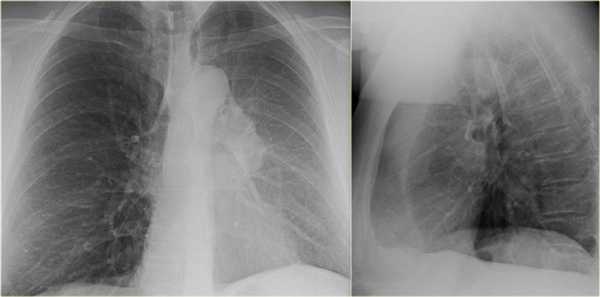

- Минимальное уменьшение объема легкого без подъема левого купола диафрагма.

- В загрудинном пространстве визуализируются изменения высокой плотности, которые спавшейся верхней доли левого легкого.

- Корень левого легкого патологичен, что может соответствовать образованию, обтурирующее просвет бронха.

- Выше перечисленные находки наводят на мысль, что это ателектаз верхней доли левого легкого.

На КТ снимках синей стрелкой указан долевой ателектаз, а красной стрелкой опухоль, которая обтурирует левый верхний долевой бронх (центральный рак легкого.

Ателектаз верхней доли левого легкого с типичным симптомом воздушного серпа (Luftsichel sign — luft(air)+sichel(sickle)), обусловленный гипервентиляцией верхнего сегмента нижней доли левого легкого на фоне коллапса верхний доли левого легкого. Гипервентилируемый

сегмент визуализируется на прямой рентгенограмме от дуги аорты до апикальной части легкого.